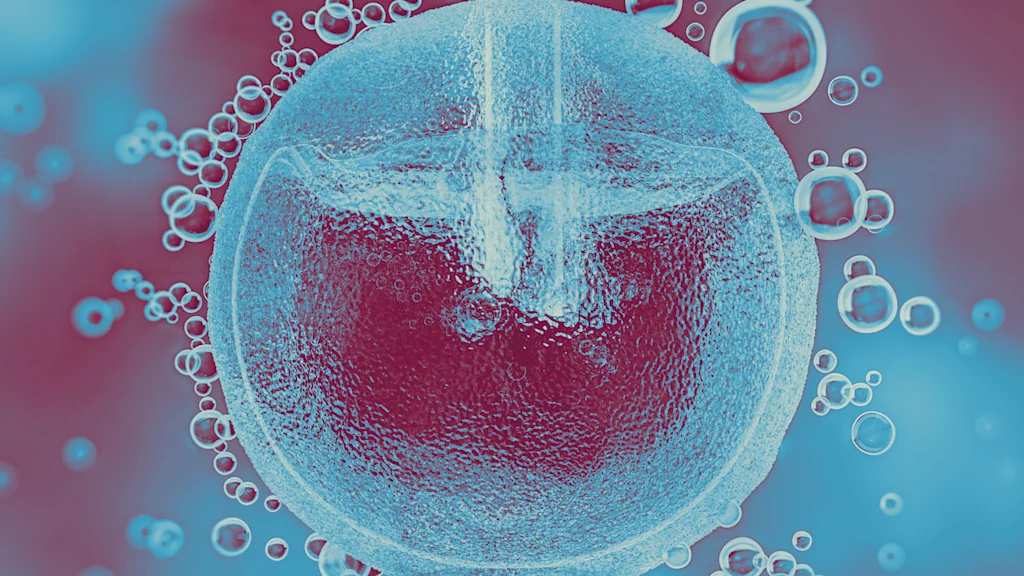

In 2023, over 40,000 women froze their eggs, a costly process averaging $20,000 per cycle, which many cannot afford. This trend reflects delayed family building and the choice of single motherhood. The financial burden of egg freezing, often exceeding $50,000, poses a significant challenge for career-driven women in their thirties. This issue is not only personal but also a public-policy failure with macroeconomic implications, as it affects the labor force participation of educated, high-skill workers, contributing to America's declining fertility rates.